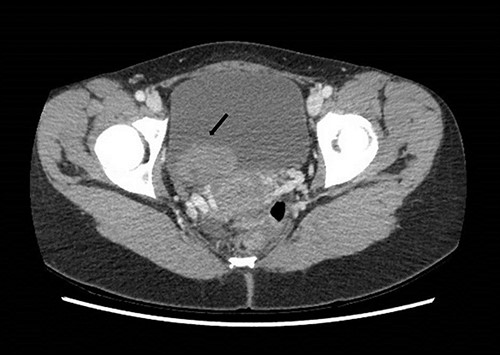

To investigate the bleeding source, she subsequently had a CT renal angiogram 3 days later that showed a narrow angle between origin of SMA and the aorta (Fig. 3) with multifocal areas of hypoattenuation throughout the left renal cortex (Fig. 4). It showed a compression ratio of 3.25 (diameter of pre-compressed vein =6.5 mm; diameter of compressed vein =2 mm) (Fig. 5).

Computed tomography angiogram on presentation showing pre-compressed LRV (right arrow); and compressed LRV (left arrow).

Computed tomography angiogram 6 months later showing pre-compressed LRV (right arrow); and compressed LRV (left arrow), but resolution of the congestion and swelling of the left kidney.